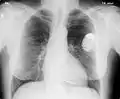

Електрокардіостимуля́тор — це пристрій, що виконує завдання штучного синоатріального вузла серця (або кардіовертер-дефібрилятор), який імплантується (вживляється) людині з метою відновлення та нормалізації порушень ритму серця.